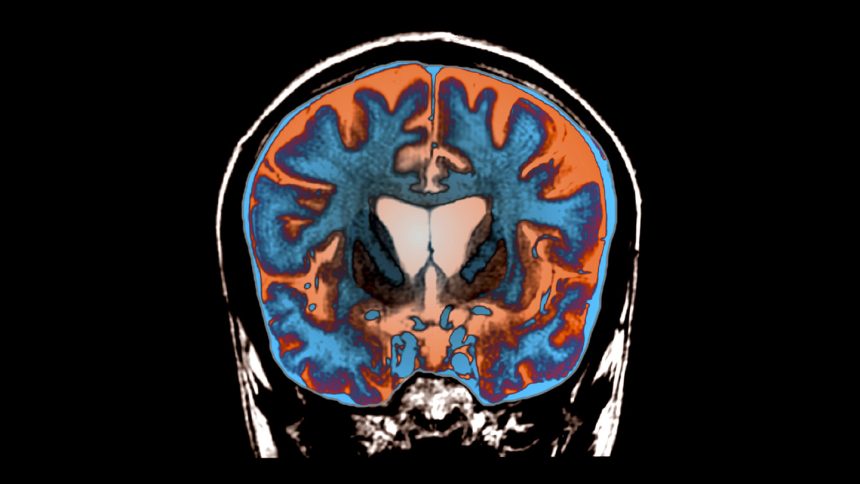

At present, Huntington’s disease lacks effective treatment options or cures, affecting approximately 7 out of every 100,000 individuals. This neurological disorder results from a specific mutation in the huntingtin gene. In cases of Huntington’s, the mutated gene results in an elongated protein that becomes toxic. According to Russell Snell, a geneticist at the University of Auckland who was not involved in the current study, “The elongated huntingtin protein aggregates in the brain, leading to the degeneration of cells in critical regions responsible for voluntary movement.”

In the study, Wild and his team, in collaboration with the Dutch pharmaceutical company uniQure, implemented a strategy involving microRNA—tiny RNA segments capable of initiating the breakdown of huntingtin RNA before it culminates in protein formation. Prior trials had attempted to deliver these RNAs directly, but they failed due to improper administration methods, such as injecting them into the cerebrospinal fluid which hindered their required penetration into specific brain regions.

This particular study, however, utilized direct brain injections, with the viral vectors “infecting” brain neurons with the RNA. “The virus effectively transforms the neuron into a factory that produces a molecule instructing it not to synthesize the huntingtin protein,” explains Wild.

During meticulous surgeries lasting between 12 to 18 hours, 17 patients showing early symptoms of Huntington’s received viral injections at three targeted locations on both sides of the brain. Over a period of 36 months, the research team monitored 12 of these patients, assessing their motor function, attention span, working memory, and daily living capabilities. “It was a heroic effort, both by the participating patients and the medical professionals,” commends Snell.